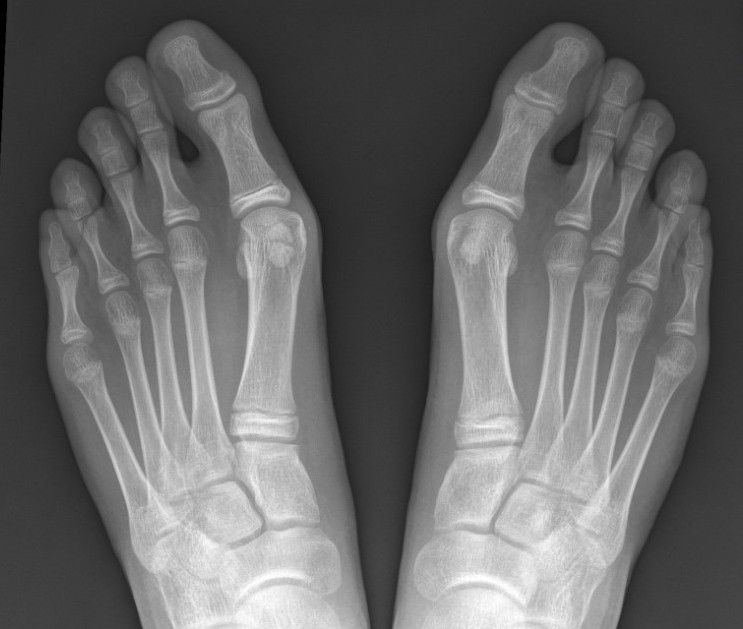

X-ray

Growth plates open

Congruent joint

Increased DMMA

Oblique first TMT joint with metatarsus adductus

Hallux valgus interphalangeus